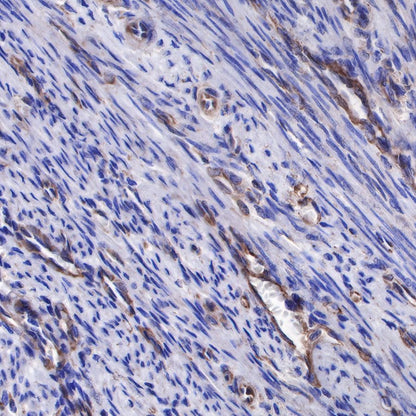

IHC shows positive staining in paraffin-embedded human endometrial cancer. Anti-sFlt-1/VEGF Receptor 1 antibody was used at 1/1000 dilution, followed by a HRP Polymer for Mouse & Rabbit IgG (ready to use). Counterstained with hematoxylin. Heat mediated antigen retrieval with Tris/EDTA buffer pH9.0 was performed before commencing with IHC staining protocol.